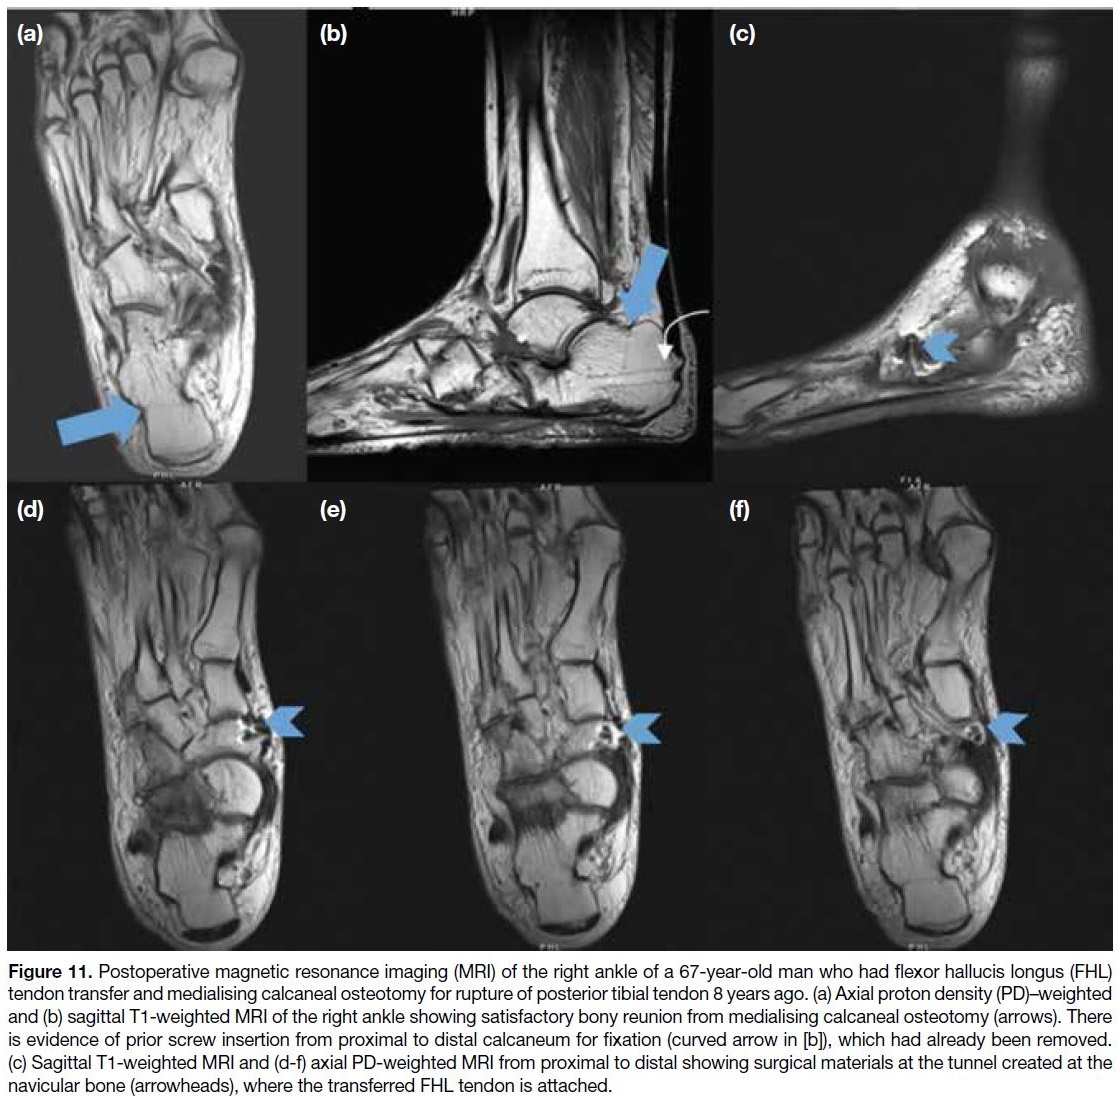

Figure 11. Postoperative magnetic resonance imaging (MRI) of the right ankle of a 67-year-old man who had flexor hallucis longus (FHL)

tendon transfer and medialising calcaneal osteotomy for rupture of posterior tibial tendon 8 years ago. (a) Axial proton density (PD)–weighted

and (b) sagittal T1-weighted MRI of the right ankle showing satisfactory bony reunion from medialising calcaneal osteotomy (arrows). There

is evidence of prior screw insertion from proximal to distal calcaneum for fixation (curved arrow in [b]), which had already been removed.

(c) Sagittal T1-weighted MRI and (d-f) axial PD-weighted MRI from proximal to distal showing surgical materials at the tunnel created at the

navicular bone (arrowheads), where the transferred FHL tendon is attached.